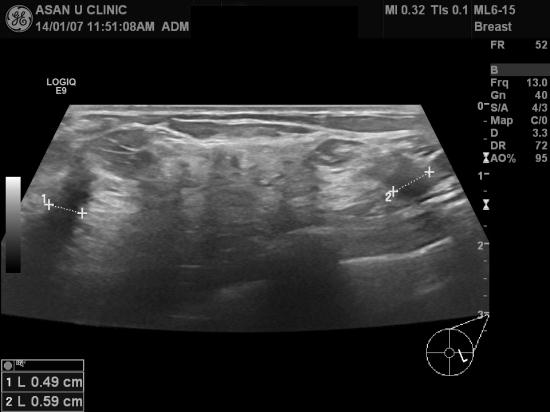

아산유외과 개원 후 54번째 유방암 진단.

건강검진으로 실시한 유방검진상 이상소견있어 내원한

52세 여성분입니다.

본원 유방초음파로 좌측유방에 0.6cm미만의 두개의 혹을 찾아 조직검사를 시행하였고

겨드랑이에는 림프절의 비대소견 없어 세침검사를 하지 않았읍니다.

유방의 두 혹 모두 침윤성 유관암으로 나와

치료위해 전원되었습니다.

아주 작은 혹이었지만

만져지지도 않지만

적절한 건강검진 덕분에 조기진단에 성공한 예입니다.

빠른쾌유를 기도합니다.